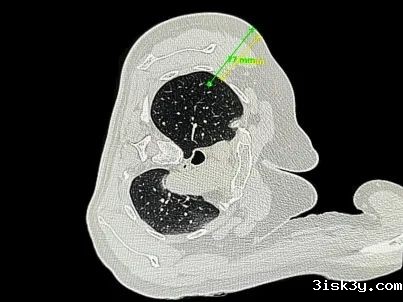

随着机器人扫描的同时,影像即刻传输至穿刺手术导航定位系统,系统对其肺部进行二维图像与三维模型的重建。同轴针准确到达规划位置,医生对其肺部病变组织进行了活检取样操作,没有给患者造成任何相关并发症。

本次研发的穿刺手术导航机器人采用“CT影像和智能传感一体化技术”,一次扫描,系统就可完成患者坐标与定位系统坐标系的配准,再根据手术路径规划,即可实现穿刺器械的准确导航定位。